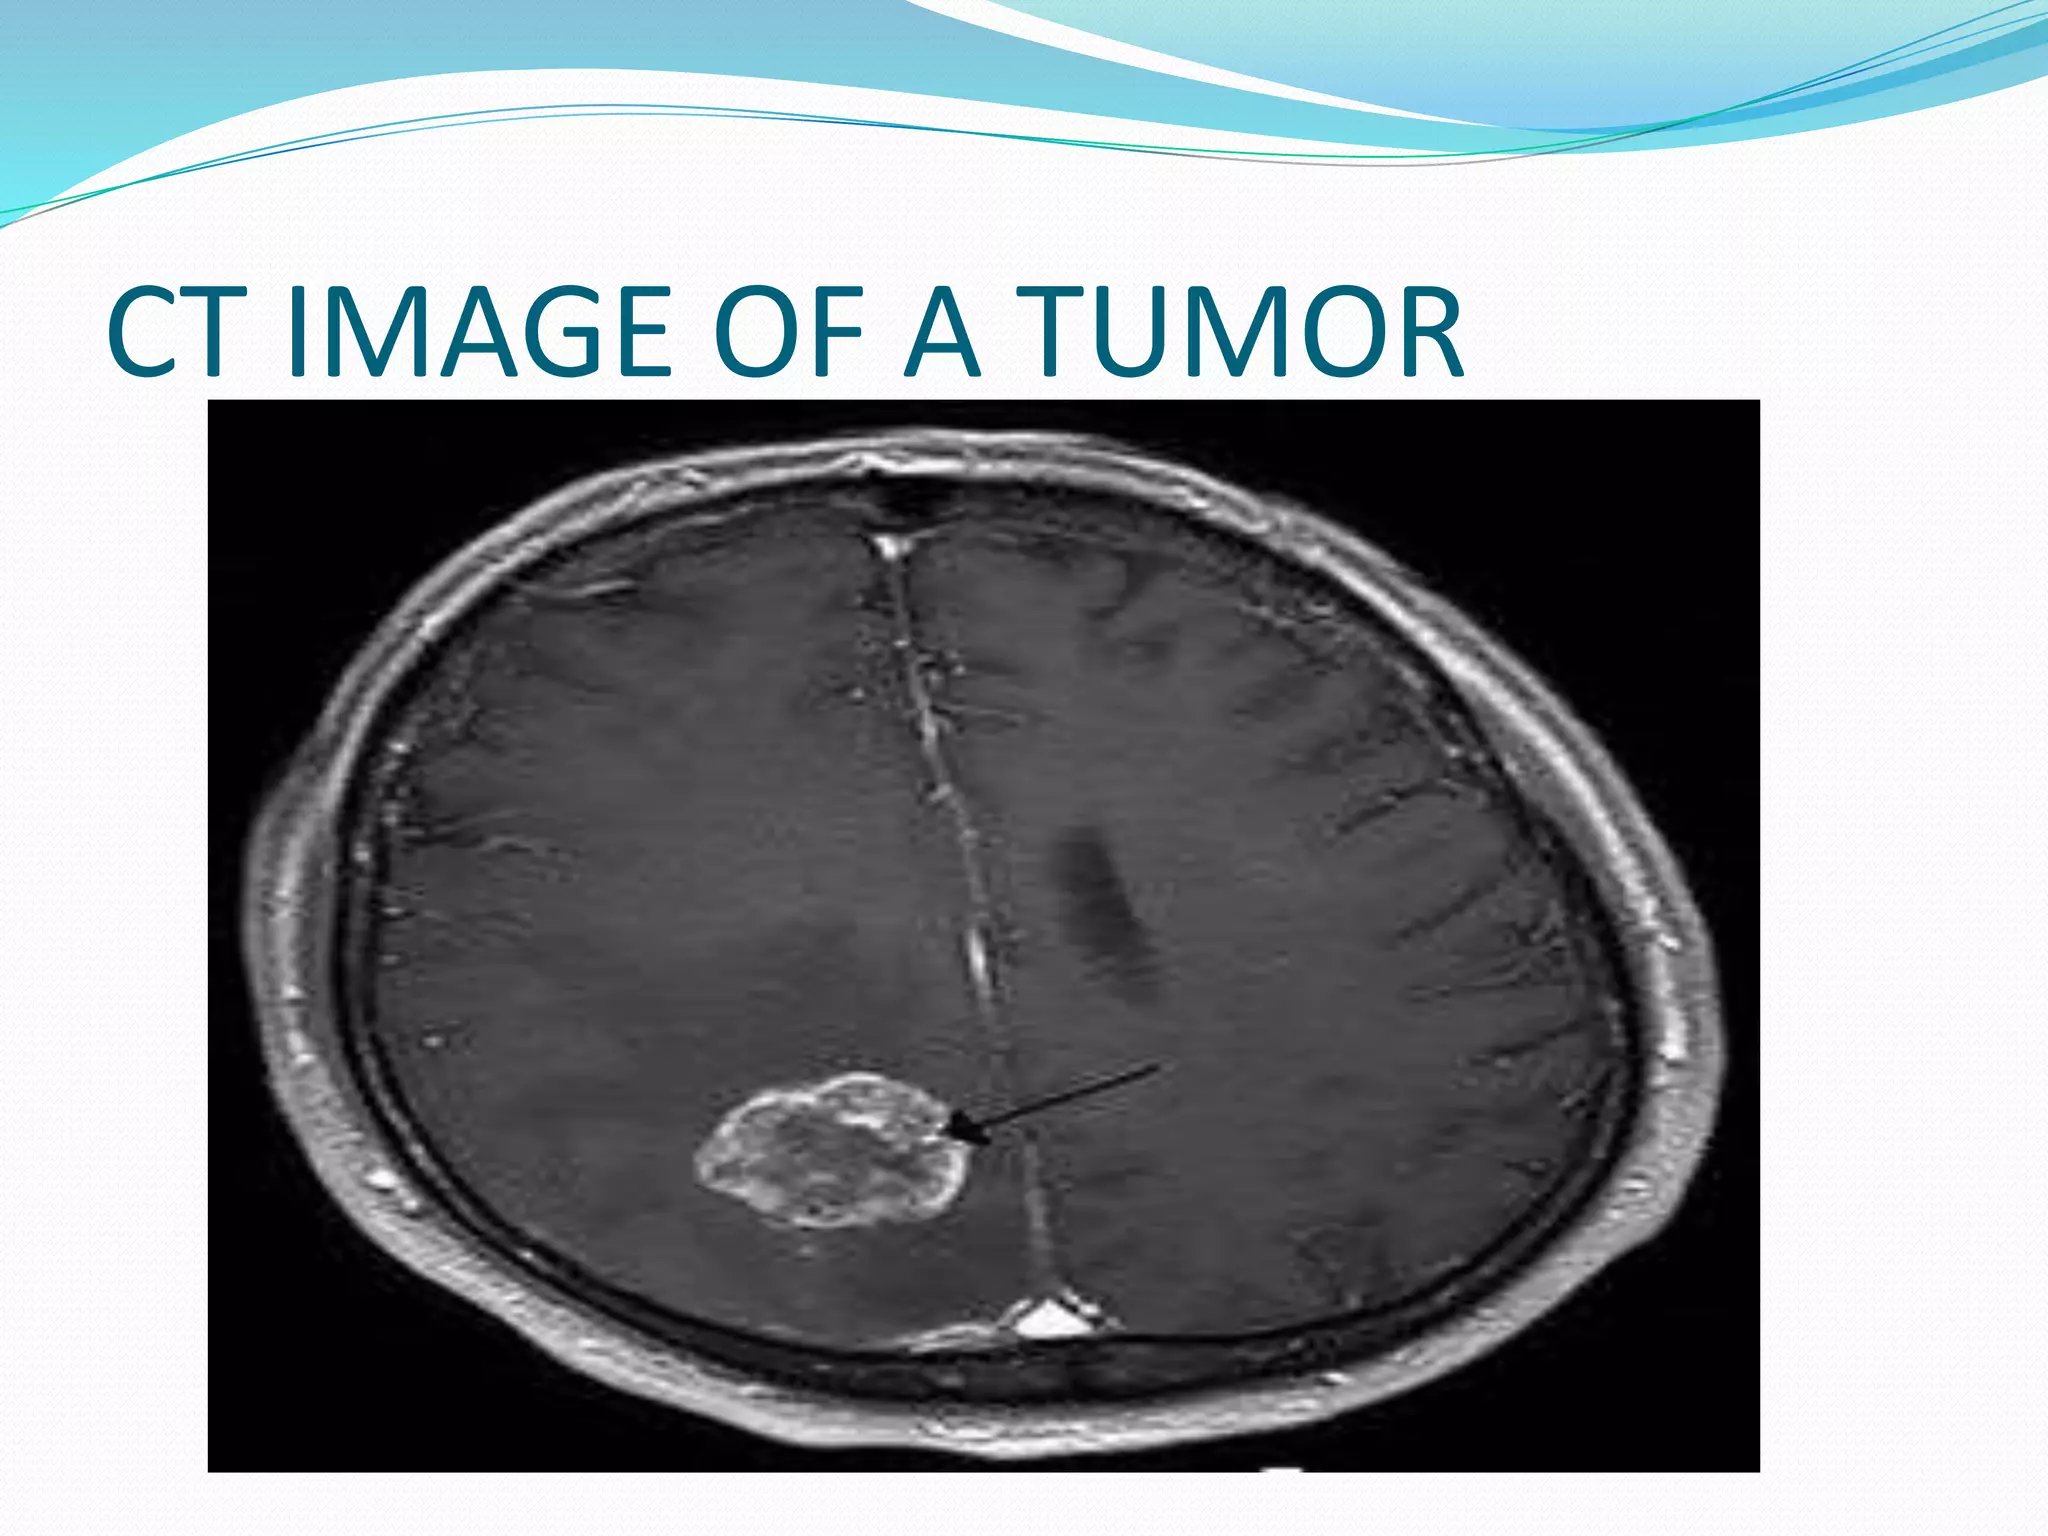

Magnetic resonance imaging

 MRI: localizes the lesion and assesses the amount

of edema and mass effect on surrounding

structures; preferred over CT because it evaluates

tumors in three planes: axial, coronal, and sagittal;

in addition, it provides greater anatomic detail

than CT,